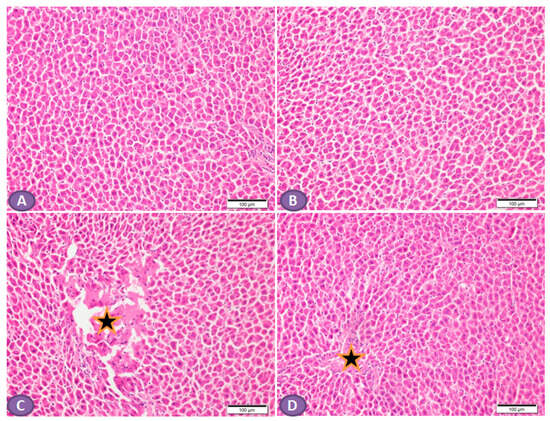

Histopathological examination of the H&E-stained liver sections of nondiabetic rats showed normal liver tissue with normal features of the architecture of hepatic lobules and portal tracts. (Figure 4A,B). Liver sections from diabetic rats revealed multiple patches of hepatic degeneration with the loss of a group of hepatocytes, inflammatory cellular infiltrations, and hepatocyte cytoplasmic degeneration (Figure 4C). On the other hand, sections from the liver of diabetic rats receiving ST showed a marked decrease in inflammatory cellular infiltrations; most of the hepatocytes were apparently with normal cytoplasm and nuclei (Figure 4D).

Figure 4.

Photomicrograph of H&E-stained liver section, scale bar = 100 µm. (A,B) represent normal nondiabetic control liver and liver of rat who received ST, respectively, showing normal histological architecture of hepatic lobules and portal tracts. Hepatocytes and the hepatic blood sinusoid are in normal state. (C) represents a liver section from rat receiving STZ as a model of diabetes, showing multiple patches of hepatic degeneration with loss of group of hepatocytes (star). The surrounding tissues show inflammatory cellular infiltrations and hepatocyte cytoplasmic degeneration. Some hepatocytes show nuclear pyknosis. (D) represents liver from diabetic rat who received ST, showing marked decrease in inflammatory cellular infiltrations; most hepatocytes are apparently within normal cytoplasm and nuclei. There is recovery of the hepatic lobular architecture. The degenerated patches decreased in number and size (star). ST, Sitagliptin; STZ, Streptozotocin.

In the scope of this study, the AST and ALT level was considered the initial indicator for liver injury [47]. The results revealed the release of liver enzymes such as ALT and AST, which were increased in T2DM rats compared to the normal control group and reduced with ST treatment. ST has a protective effect on the liver, manifested as an improvement in liver transaminases [48]. These results were supported by histopathological examination findings, which disclosed marked hepatic injury in the T2DM group. The biochemical and histological alterations associated with STZ induction were significantly decreased by ST treatment, indicating that ST could effectively counteract DM-induced liver cell injury.